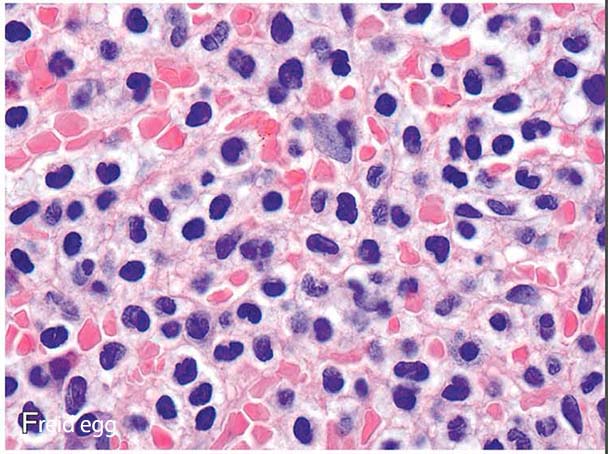

fried egg.jpg

脾臓: 脾臓は,腫瘍細胞の赤脾髄びまん性浸潤と拡大により著明な腫大を示し,白脾髄の萎縮を伴う.*45腫瘍浸潤は,細胞質が明瞭な中型細胞の単調な集団で構成され,"目玉焼き "のような外観を呈する(Fig3).拡張した洞は赤血球で満たされ,"血の池"("仮性洞 "とも呼ばれる)を形成することがある。